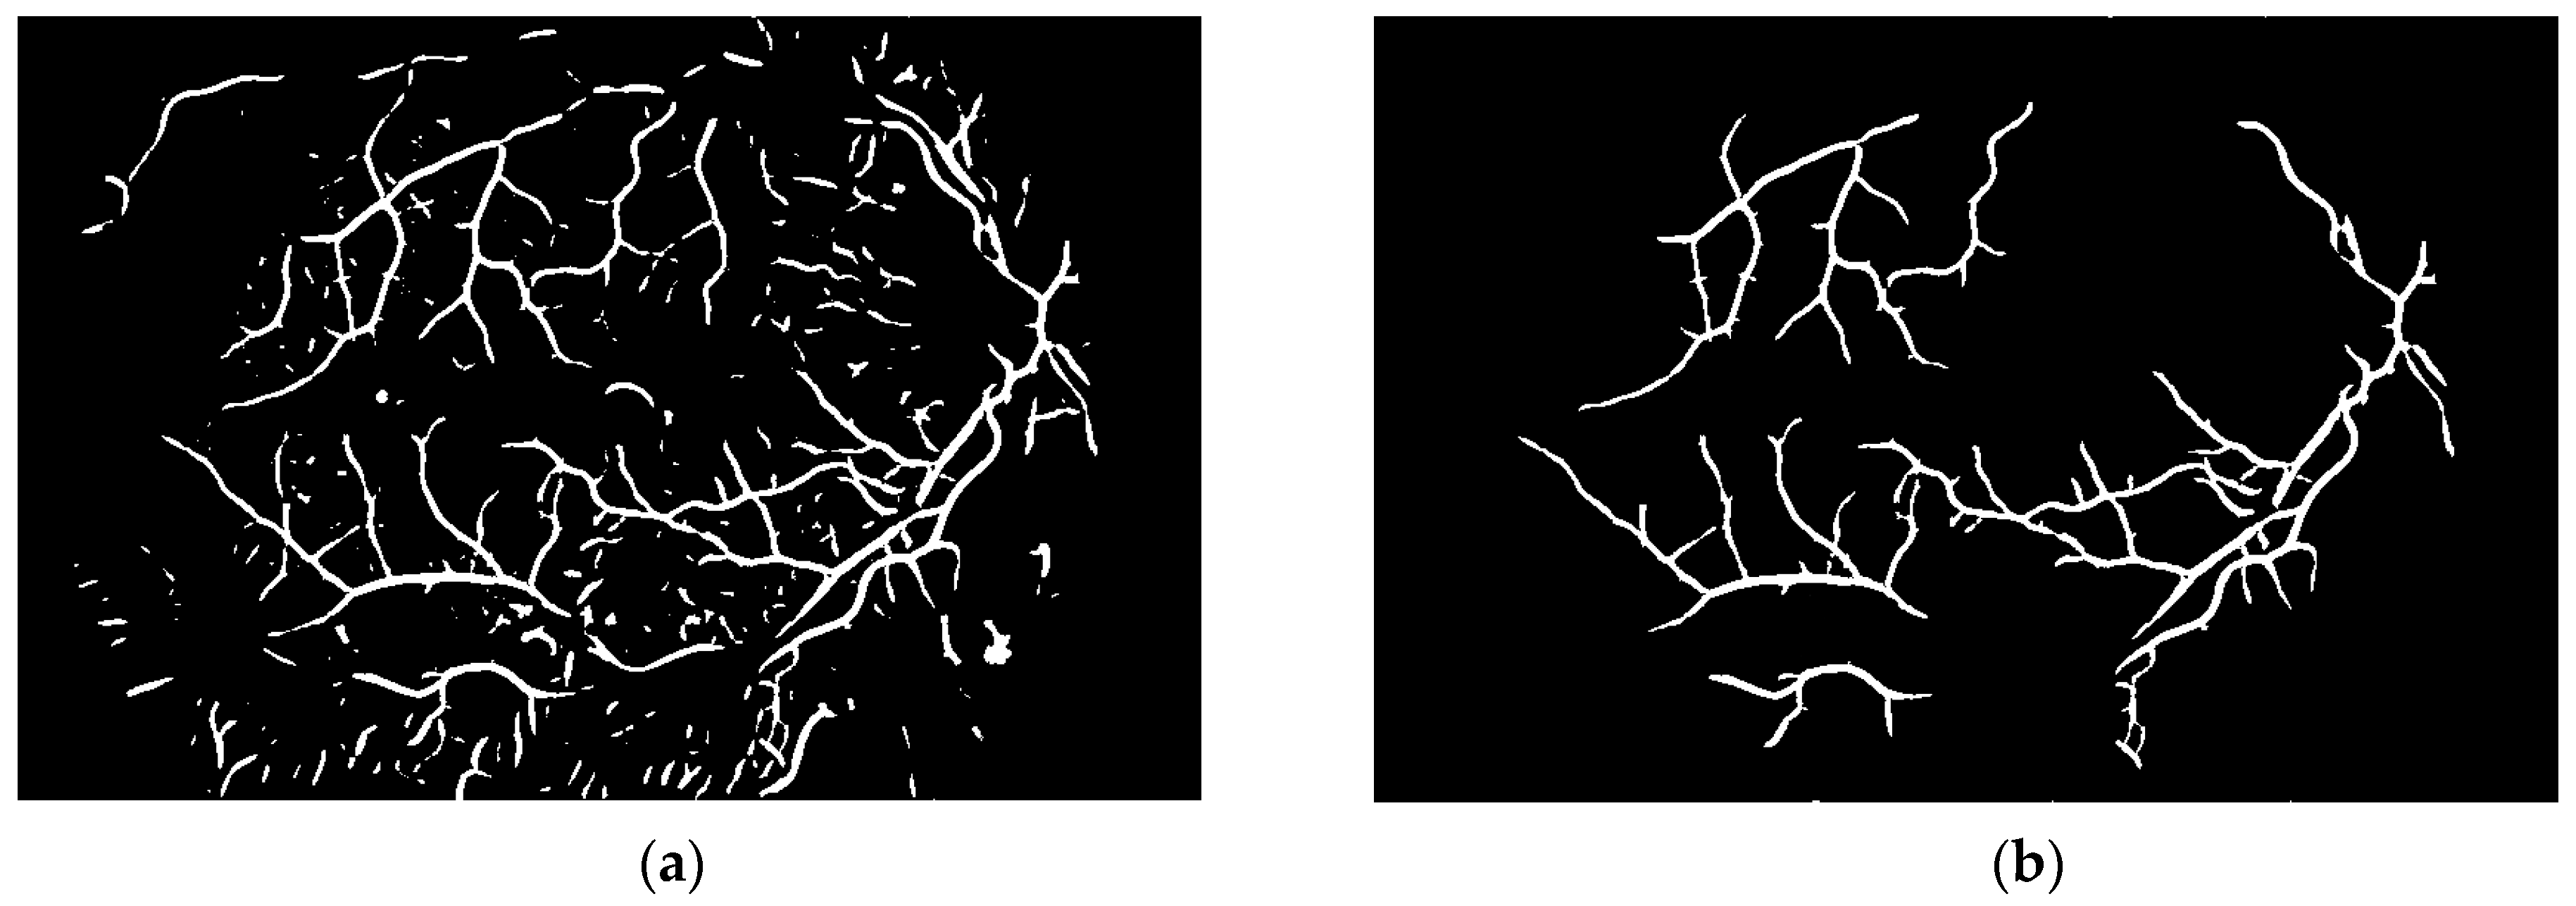

To obtain proper vascular patterns, a local entropy binarization algorithm was used to get proper white veins on a black background. However, this has caused a few small elements that do not belong to retinal veins to be shown in the image, alongside the marked veins. Additional elements are removed on the basis of their length. If they are too short (the length in pixel number is selected arbitrarily), they are deleted–we assume that these elements are not parts of real veins. The results of both of these steps are presented in Figure 13.

Via this step, the vascular pattern of the processed retina was obtained. In the form presented in Figure 13b, it will be applied to the obtained image after the preprocessing stage (Figure 8b). Both of these images are considered in the next module.

Figure 13. Image (a) after binarization and (b) after short vessel removal.